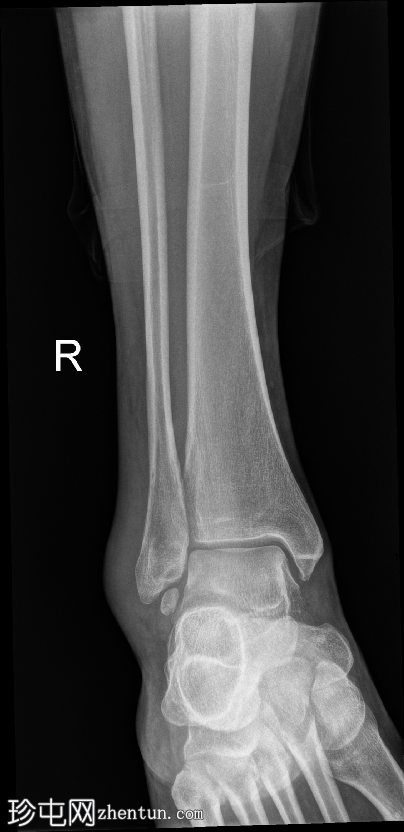

正位片

腓骨远端下方可见一皮质完整的圆形小骨,符合腓骨下骨的特征。其光滑的边缘和皮质化程度提示为慢性副骨,而非急性撕脱骨折碎片。外踝上方可见局部软组织肿胀,表现为该区域软组织密度增高和隆起。

前后关节窝轻度扩张,提示踝关节积液。未见急性骨折或脱位。关节间隙清晰,对位正常。